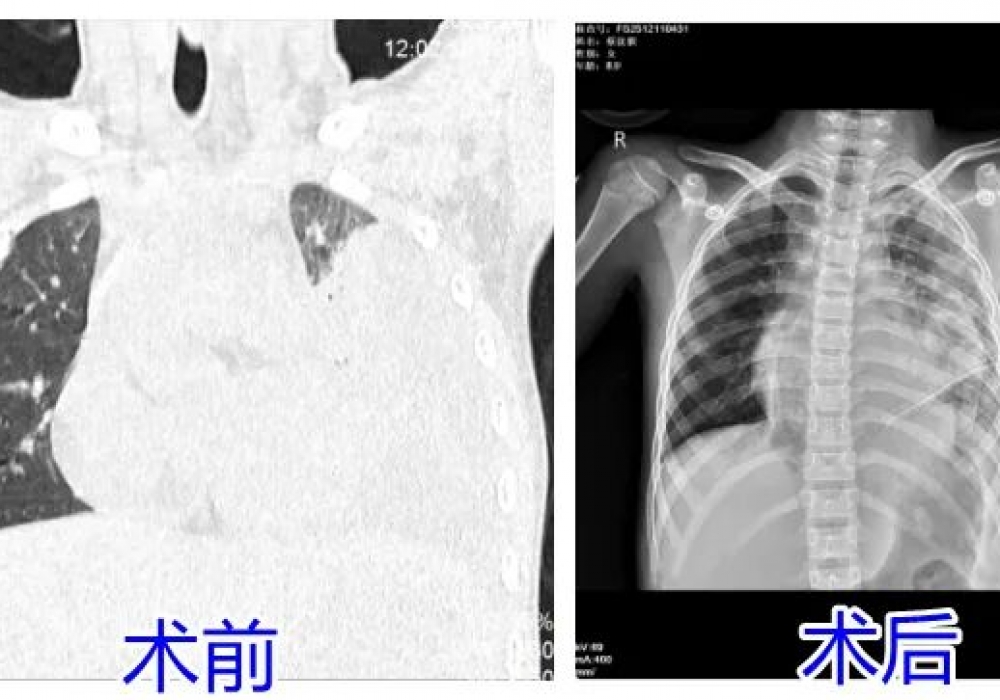

- 6岁女孩“感冒”后,喘不上气,命悬一线…… 2025-09-19 | 儿二科